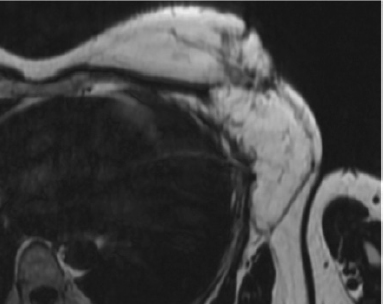

Major progress has been achieved in the radiologic diagnosis of patients with lymphedema. MR lymphangiography with T2-weighted imaging allows visualization of the anatomy of the lymphatic system with greater sensitivity than lymphoscintigraphy and potentially without the need for any injection, 1 , 2 although the use of gadolinium with venous suppression probably yields more consistent images. The ideal treatment of the affected limb should restore both function and the cosmetic appearance. Physical therapy is the most commonly performed treatment for chronic lymphedema, and many consider it the only treatment for long-term management. Certainly, it helps to control to some extent the evolution of the disease, but it is not a curative therapy.

MR lymphangiography helps identify the type of edema and is critical to deciding the best treatment option.

Identifying the problem is very important because it guides the surgeon on the optimal placement of the lymph nodes and which lymphatic pathways must be targeted during physical therapy. MR lymphangiography is the best investigation tool to evaluate the problem. The flap can be sometimes enlarged to reconstruct the breast defect and fibrotic area in the axillary or inguinal region.

Congenital lymphedema can present in various forms. Lymphoscintigraphy yields poor results and in our practice has been completely replaced by MR lymphangiography. However, this form of imaging is relatively new and is performed in only a few centers. The syndromes, hypoplastic or hyperplastic forms, and the level of the malformations are evaluated. Some individuals can present simultaneously, with both hypoplastic and hyperplastic forms in different parts of the body. VLNT is indicated in patients with hypoplasia, because lymphangiogenic proteins are contained in the transplanted nodes, and they simultaneously act as sump pumps to transfer some of the lymphatic fluid into the venous circulation. 8

Physical therapy was complementary to the surgical treatment. Compressive bandages were applied, and manual drainage was performed for the first 3 postoperative months and progressively reduced thereafter. Patients were evaluated by perimetry, volumetry, and quality of life, and preoperative and postoperative photographs were taken after 6 and 12 months and 2 and 5 years. Between 1992 and 2011, lymphoscintigraphy was performed preoperatively and 1 and 5 years postoperatively. However, the correlation with the clinical results was not always appropriate. Since 2011, MR lymphangiography has yielded superior information and excellent images of the lymphatic system.